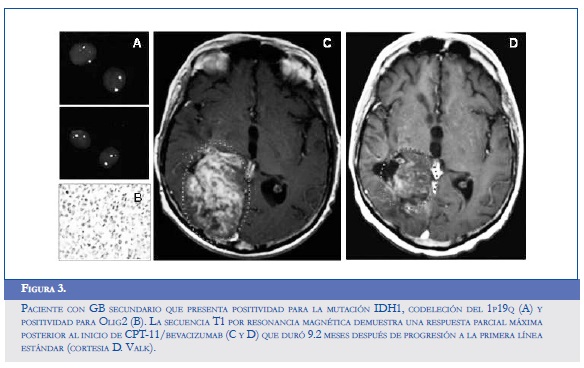

El flavopiridol, un inhibidor de múltiples ciclinas dependientes de quinasas capaz de reducir los niveles de VEGF en el microambiente hipóxico, disminuye en consecuencia la expresión del HIF-1α en las líneas celulares de gliomas U87MG y T98G, que demuestran una elevada capacidad para la invasión y la migración. La reducción de la expresión anormal del HIF también se confirmó después de exponer las células a un inhibidor del proteasoma que usualmente eleva los niveles de esta sustancia proangiogénica (54). Otros modelos celulares han encontrado potencial en el control dual del Ras y del HIF-1α a través del uso de los inhibidores de la farnesil transferasa (trans-farnesylthiosalicylic acid), los cuales también promueven una disminución en la expresión del VEGF y de la Glut-1 (glucose transporter 1), favoreciendo la normalización del proceso de invasión y la glicolisis alterada del GB (55). El radicicol (KF58333) y la geldanamicina, dos antagonistas de la HSP90 (heat shock protein 90), disminuyen la transactivación activa del HIF y promueven su degradación en células gliomatosas independientes de la concentración de oxígeno y de la pVHL (55). Algo similar ocurre al administrar vincristina, paclitaxel, 2-metoxiestradiol, algunos de los inhibidores de la topoisomerasa I y II, y de la PI3K (LY294002) y wortmanina (56). La figura 3 muestra el caso de un paciente con GB secundario que presenta positividad para la mutación IDH1, codeleción del 1p19q (A) y positividad para Olig2 (B). La secuencia T1 por resonancia magnética demuestra una respuesta parcial máxima posterior al inicio de CPT-11/bevacizumab (C y D) que duró 9,2 meses después de progresión a la primera línea estándar.